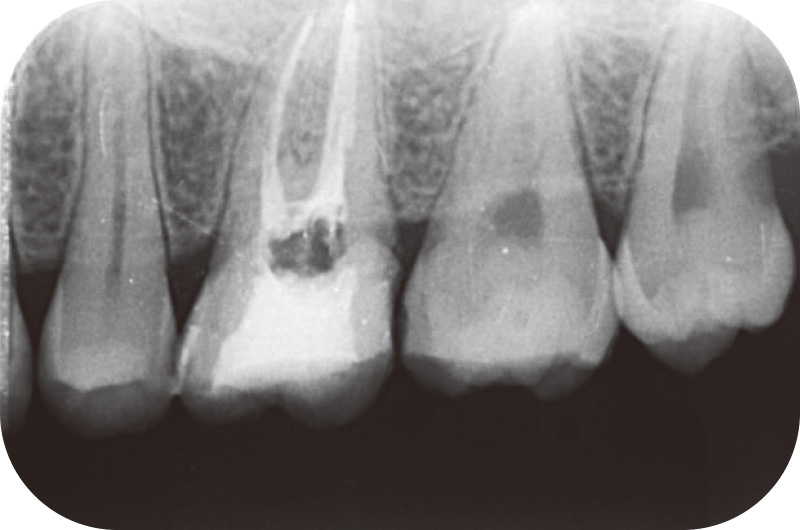

患者は20歳男性、左上臼歯部の違和感を主訴に来院した。26は以前から度々自発痛を呈していたが、しばらくすると落ち着いたため、放置していた。初診時のデンタルX線写真を示す(図3)。26に歯髄に近接する明らかなカリエスを認めた。26の診査結果は軽度の打診痛、EPT(+)、冷温刺激にてやや疼痛を認め、持続時間は30秒程度であったため、歯髄は可逆性歯髄炎、根尖周囲組織は正常と診断し、生活歯髄療法(VPT)を行った。カリエスを丁寧に除去したが、一部露髄が認められたため、直接覆髄を試みた。NaClOにて露髄面の止血を行い、止血確認後にMTAセメントにてVPTを行った。その際、マイクロスコープにて露髄面の出血を確認し、やや血流は悪いと感じたが、若年者の生活歯髄に期待し、歯髄保存を選択した(図4)。その後、しばらくは経過良好であったが、半年後に突然強度の自発痛を自覚し、EPT(-)を示したため、歯髄壊死、症状のある根尖性歯周炎と診断し、感染根管治療に踏み切った。

![[写真] 20歳男性左上初診時デンタルX線](/academic/dentalmagazine/wp-content/uploads/sites/2/2025/09/194-17_photo03.jpg)

図3 20歳男性左上初診時デンタルX線。26に歯髄に近接するカリエスを認める。 -